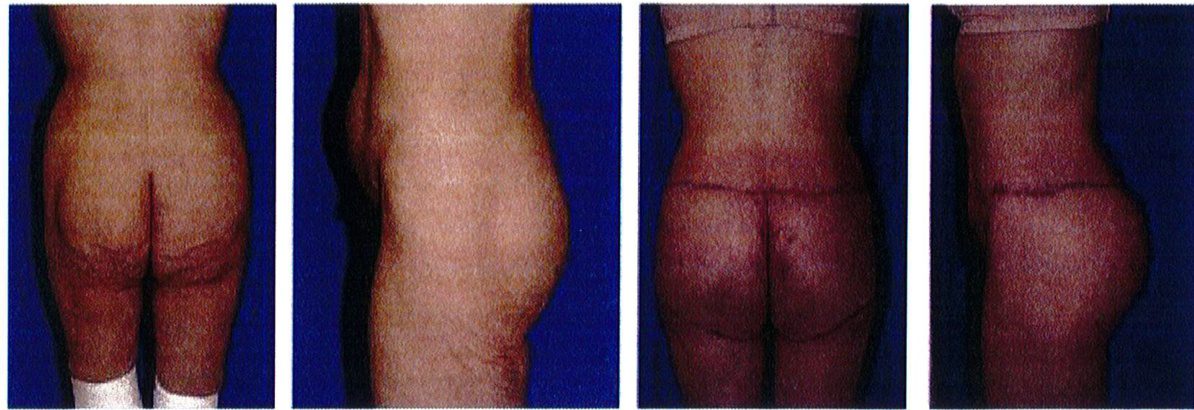

Hình. 9. Minh họa khung vuông, cao trước (trái) và sau (phải) phầu thuật chỉnh hình mông.

Hình. 12. Khung mông dạng chữ A, cao trước (bên trái) và sau (bên phải) nâng mông thẩm mỹ.

Hình. 15. Khung hình chữ V, cao với khối cơ mông lớn ngắn trước (trái) và sau (phải) phẫu thuật tạo hình.